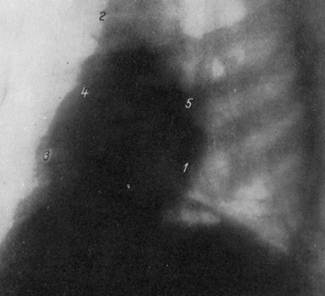

РЕНТГЕНОГРАММА НОРМАЛЬНОЙ ГРУДНОЙ КЛЕТКИ В ПЕРВОМ КОСОМ ПОЛОЖЕНИИ.

1 - дуга левого желудочка; 2 — аорта; 3 — дуга правого предсердия; 4 — дуга левого предсердия; 5 — дуга артериального конуса.